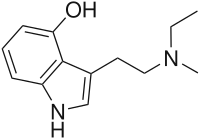

| 5-HO-MiPT | artificial | 5-OH | CH3 | CH(CH3)2 | 5-hydroxy-N-methyl-N-isopropyltryptamine | |